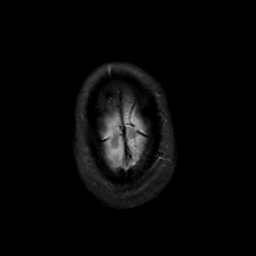

MR Study #10, April 28, 1991 -- Slice #47

[Home][Help][Clinical][Tour 1][Tour 2] Slice 47